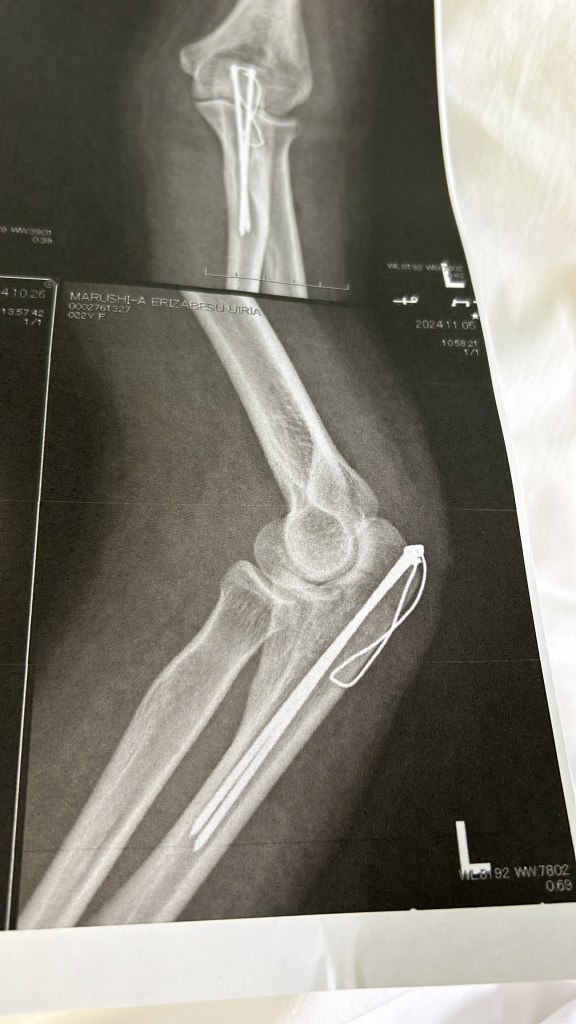

I fell behind on my entries for a number of reasons, one of which is the fact that I sustained an injury during my stay in Japan. While traveling the farm one morning, a tool fell in between the spokes of my bicycle and sent me over the handlebars, breaking and dislocating my elbow and giving me a concussion. It was mere seconds before Lee arrived behind me, guiding me back the house and treating my wounds with olive oil and basil. Immediately, my open wounds eased and I felt relief as Lee tenderly wrapped my hands and arms in cloth. It would have never dawned on me to use the herbs that could be found in our kitchen to alleviate the pain that I felt, but it was Lee’s first instinct with her knowledge of antiseptic and antibacterial plants that served medicinal purposes. Within a few hours, I was sitting in the emergency room of the Kyoto Prefecture Hospital as I listened to doctor’s discuss my injuries in a language I failed to understand. It was not until I arrived home the same night that I read “necessary surgery following break” that I found myself at a loss for words. In that moment, I did not feel strong enough to do this on my own. How was I to endure a surgery in a foreign country with a language barrier and an injury I did not fully understand? Shortly after my hospital visit, I contacted my fellowship foundation and alerted them to what happened. I was given the greenlight to travel back to Arkansas, something I had originally agreed to not doing unless a dire circumstance occurred. There I found myself in a dire circumstance, yet I could not bring myself to look at flights home.

I visited a number of hospitals before I was scheduled to have surgery, which was delayed due to severe swelling. Prior to this, I had never broken a bone. The healthcare and treatment I received in Japan was exceptional. The week leading up to my surgery, Lee treated me with balms and teas that soothed my pain. The frustration I felt with a lack of movement, something I still struggle with today, was also relieved as Lee helped me each step of the way. One night in particular, I asked Lee to braid my hair. She agreed without hesitation as I handed her the hairband that was wrapped around my wrist. As she sectioned my hair into three pieces, she told me of a dream she had where a childhood friend of hers braided her hair. “I am not sure what it means,” she said. Lee had not seen this friend in years, and yet she spoke of this dream that she remembered with fondness. Although she said her friend had never braided her hair before, I suggested that maybe she dreamt of this because of the amount of gentleness and delicacy she described her friend to have, and the trust that came along with this. In that moment, I reflected on how I, too, felt similarly about the woman who I found braiding my hair. Just as Robin Wall Kimmerer states in “Braiding Sweetgrass: Indigenous Wisdom, Scientific Knowledge, and the Teachings of Plants”:

My surgeon, Dr. Yoshihiro Kotoura, who I met before my admission, also provided a sense of safety and understanding as he told me a story of a woman he met while he was studying at the Mayo Clinic in New York. He spoke to me about a late night at the subway station when he was without local currency, which led the staff telling him he could not travel without USD. An American woman approached him and handed him his bus fare, and wished him well on his journey. “Because of this woman’s kindness to me as a foreigner, it is my honor to treat you while you are a foreigner in Japan.” I was brought to tears by this, and he assured me that I would be well on my way to the UK come December. Further, he ensured that my family was aware of my situation and that I had support throughout the process despite being alone. The nurses, including Yuzuha who spoke with me enthusiastically through Google translate, made me feel at home while being abroad. Although my surgery proved to be painful and harsh with only Tylenol to treat the pain postoperative, my arm has healed tremendously since my surgery in early November.